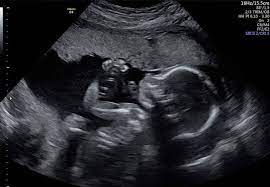

تعداد نوزادان را بشمارید: ممکن است با شوک حاملگی بیش از یک نوزاد از سونوگرافی خارج شوید.

آنومالی اسکن یا سونوگرافی سطح دوم، یک بررسی دقیق از آناتومی جنین است که معمولاً بین هفتههای ۱۸ تا ۲۲ بارداری انجام میشود. در این مرحله از رشد جنین، بسیاری از اندامها به اندازهای رشد کردهاند که میتوان ساختار آنها را به وضوح مشاهده و بررسی کرد. این سونوگرافی برخلاف اسکنهای اولیه که بیشتر برای تعیین سن بارداری یا بررسی ضربان قلب انجام میشوند، تمرکز اصلیاش بر شناسایی ناهنجاریهای ساختاری در جنین است.